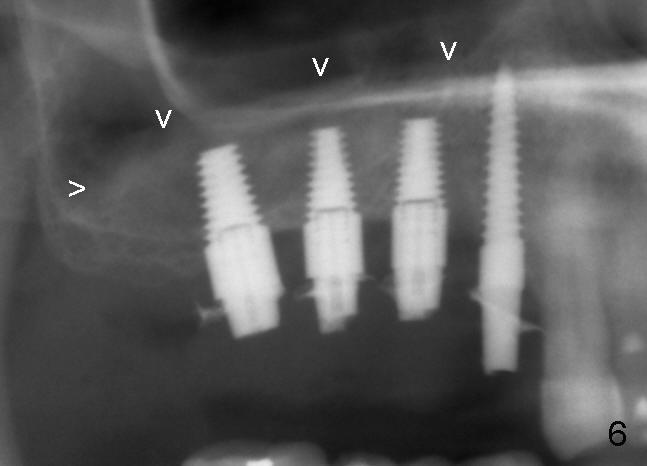

When the patient arrives at the office for sinus graft, the most important thing for her is to have two provisionals in the premolar region postop (Fig.1: #4,5; >: suture left from previous surgery). These existing provisionals appear to interfere with sinus lateral window incision and removed. So is the mini-implant.